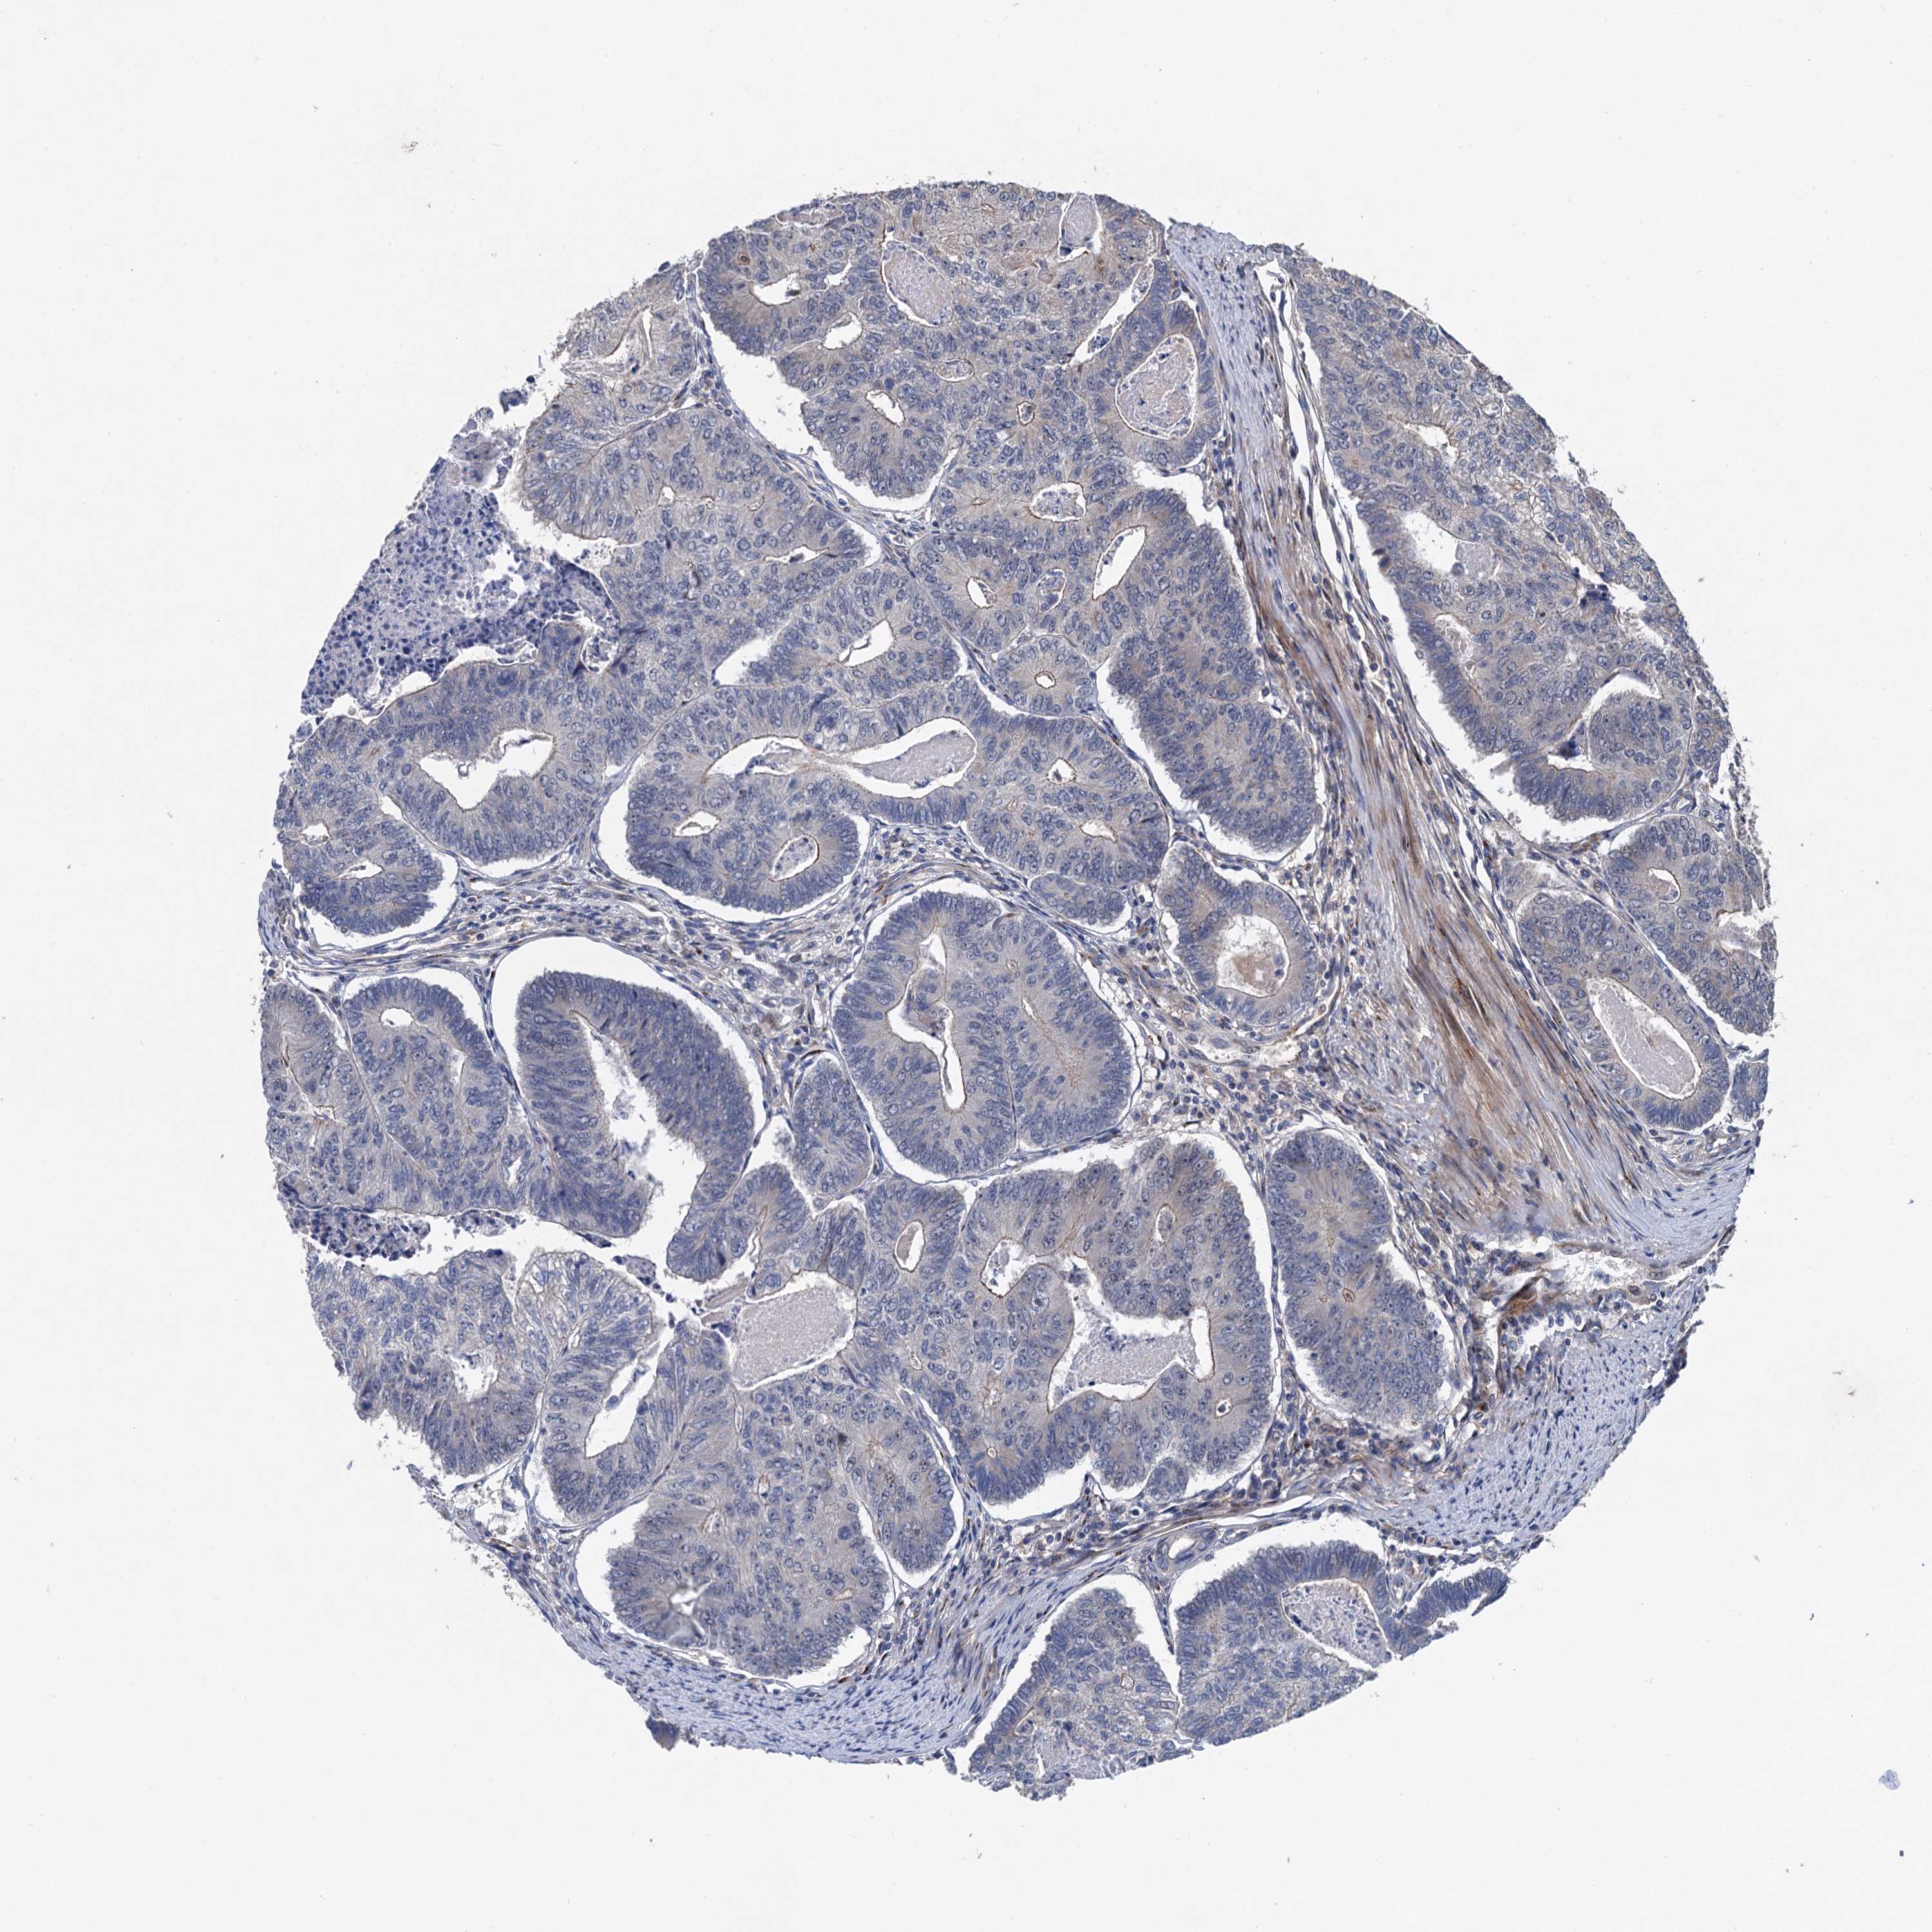

CANCER COLORECTAL CANCER Show tissue menu

Colorectal cancer

Human cancer

Colon adenocarcinoma